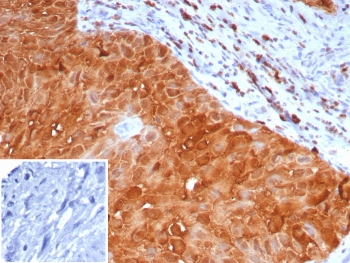

Cathepsin D Antibody

| Description | Cathepsin D Antibody |

| Tested applications | FC, ICC, IHC, IP, WB |

| Reactivity | Human, Mouse |